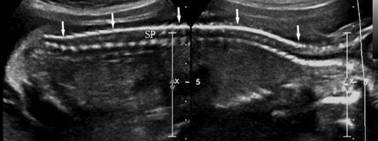

一、脊柱矢状切面

矢状面扫查可显示出脊柱的全长及其表面皮肤的覆盖情况。脊柱显示为排列整齐的串珠状平行带状强回声,自颈椎至腰椎显示为自然弓背向后的曲度,骶尾部略向后翘并逐渐变细,最后融合在一起;腹侧的带状强回声由椎体形成,背侧的带状强回声由椎弓形成,二者之间的冠状回声为椎管,颈段椎管和腰段椎管稍增宽,胸段椎管宽度基本一致(图1)。

图1胎儿脊柱失状切面声像图(右为头端,左为尾端)

14孕周~24孕周胎儿脊柱长度(SL)与孕周(GW)关系:SL (mm) = -47.2 + 7.16 × GW。